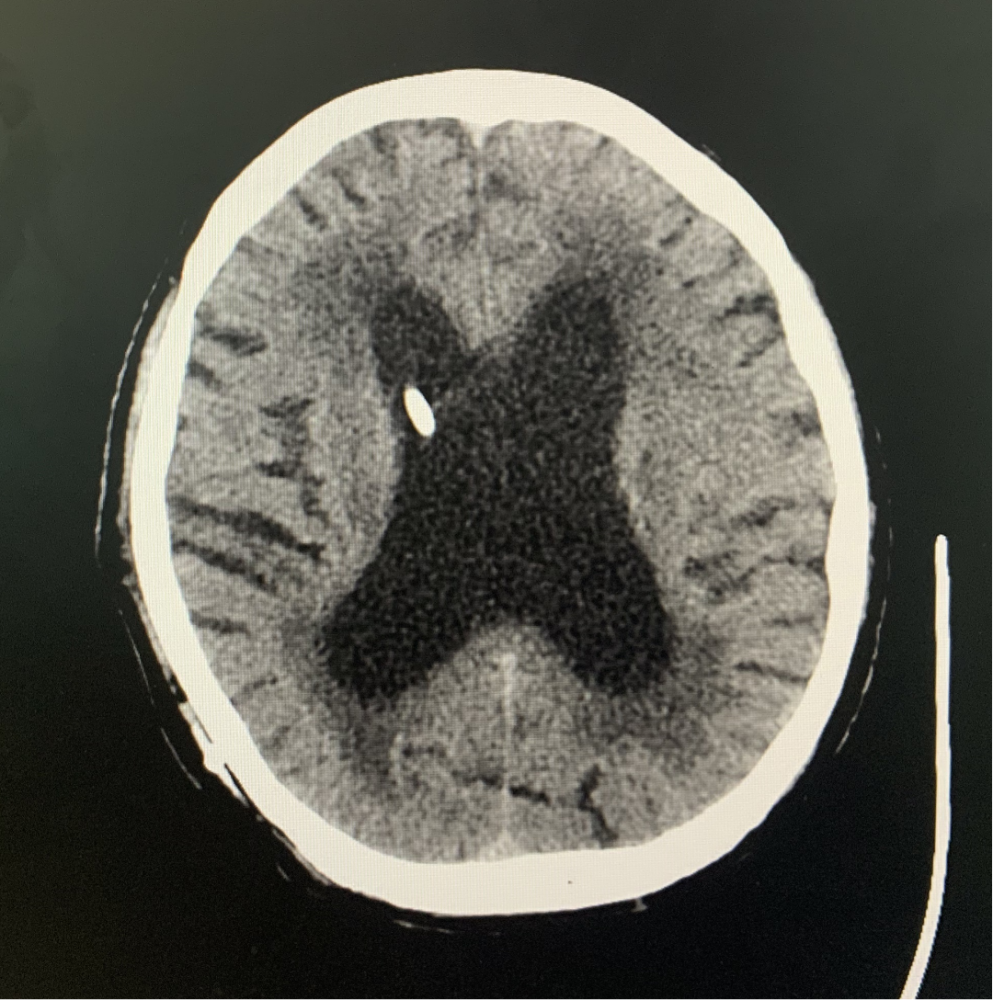

脑积水CT

脑积水ct显示,侧脑室明显扩大,脑沟脑回消失